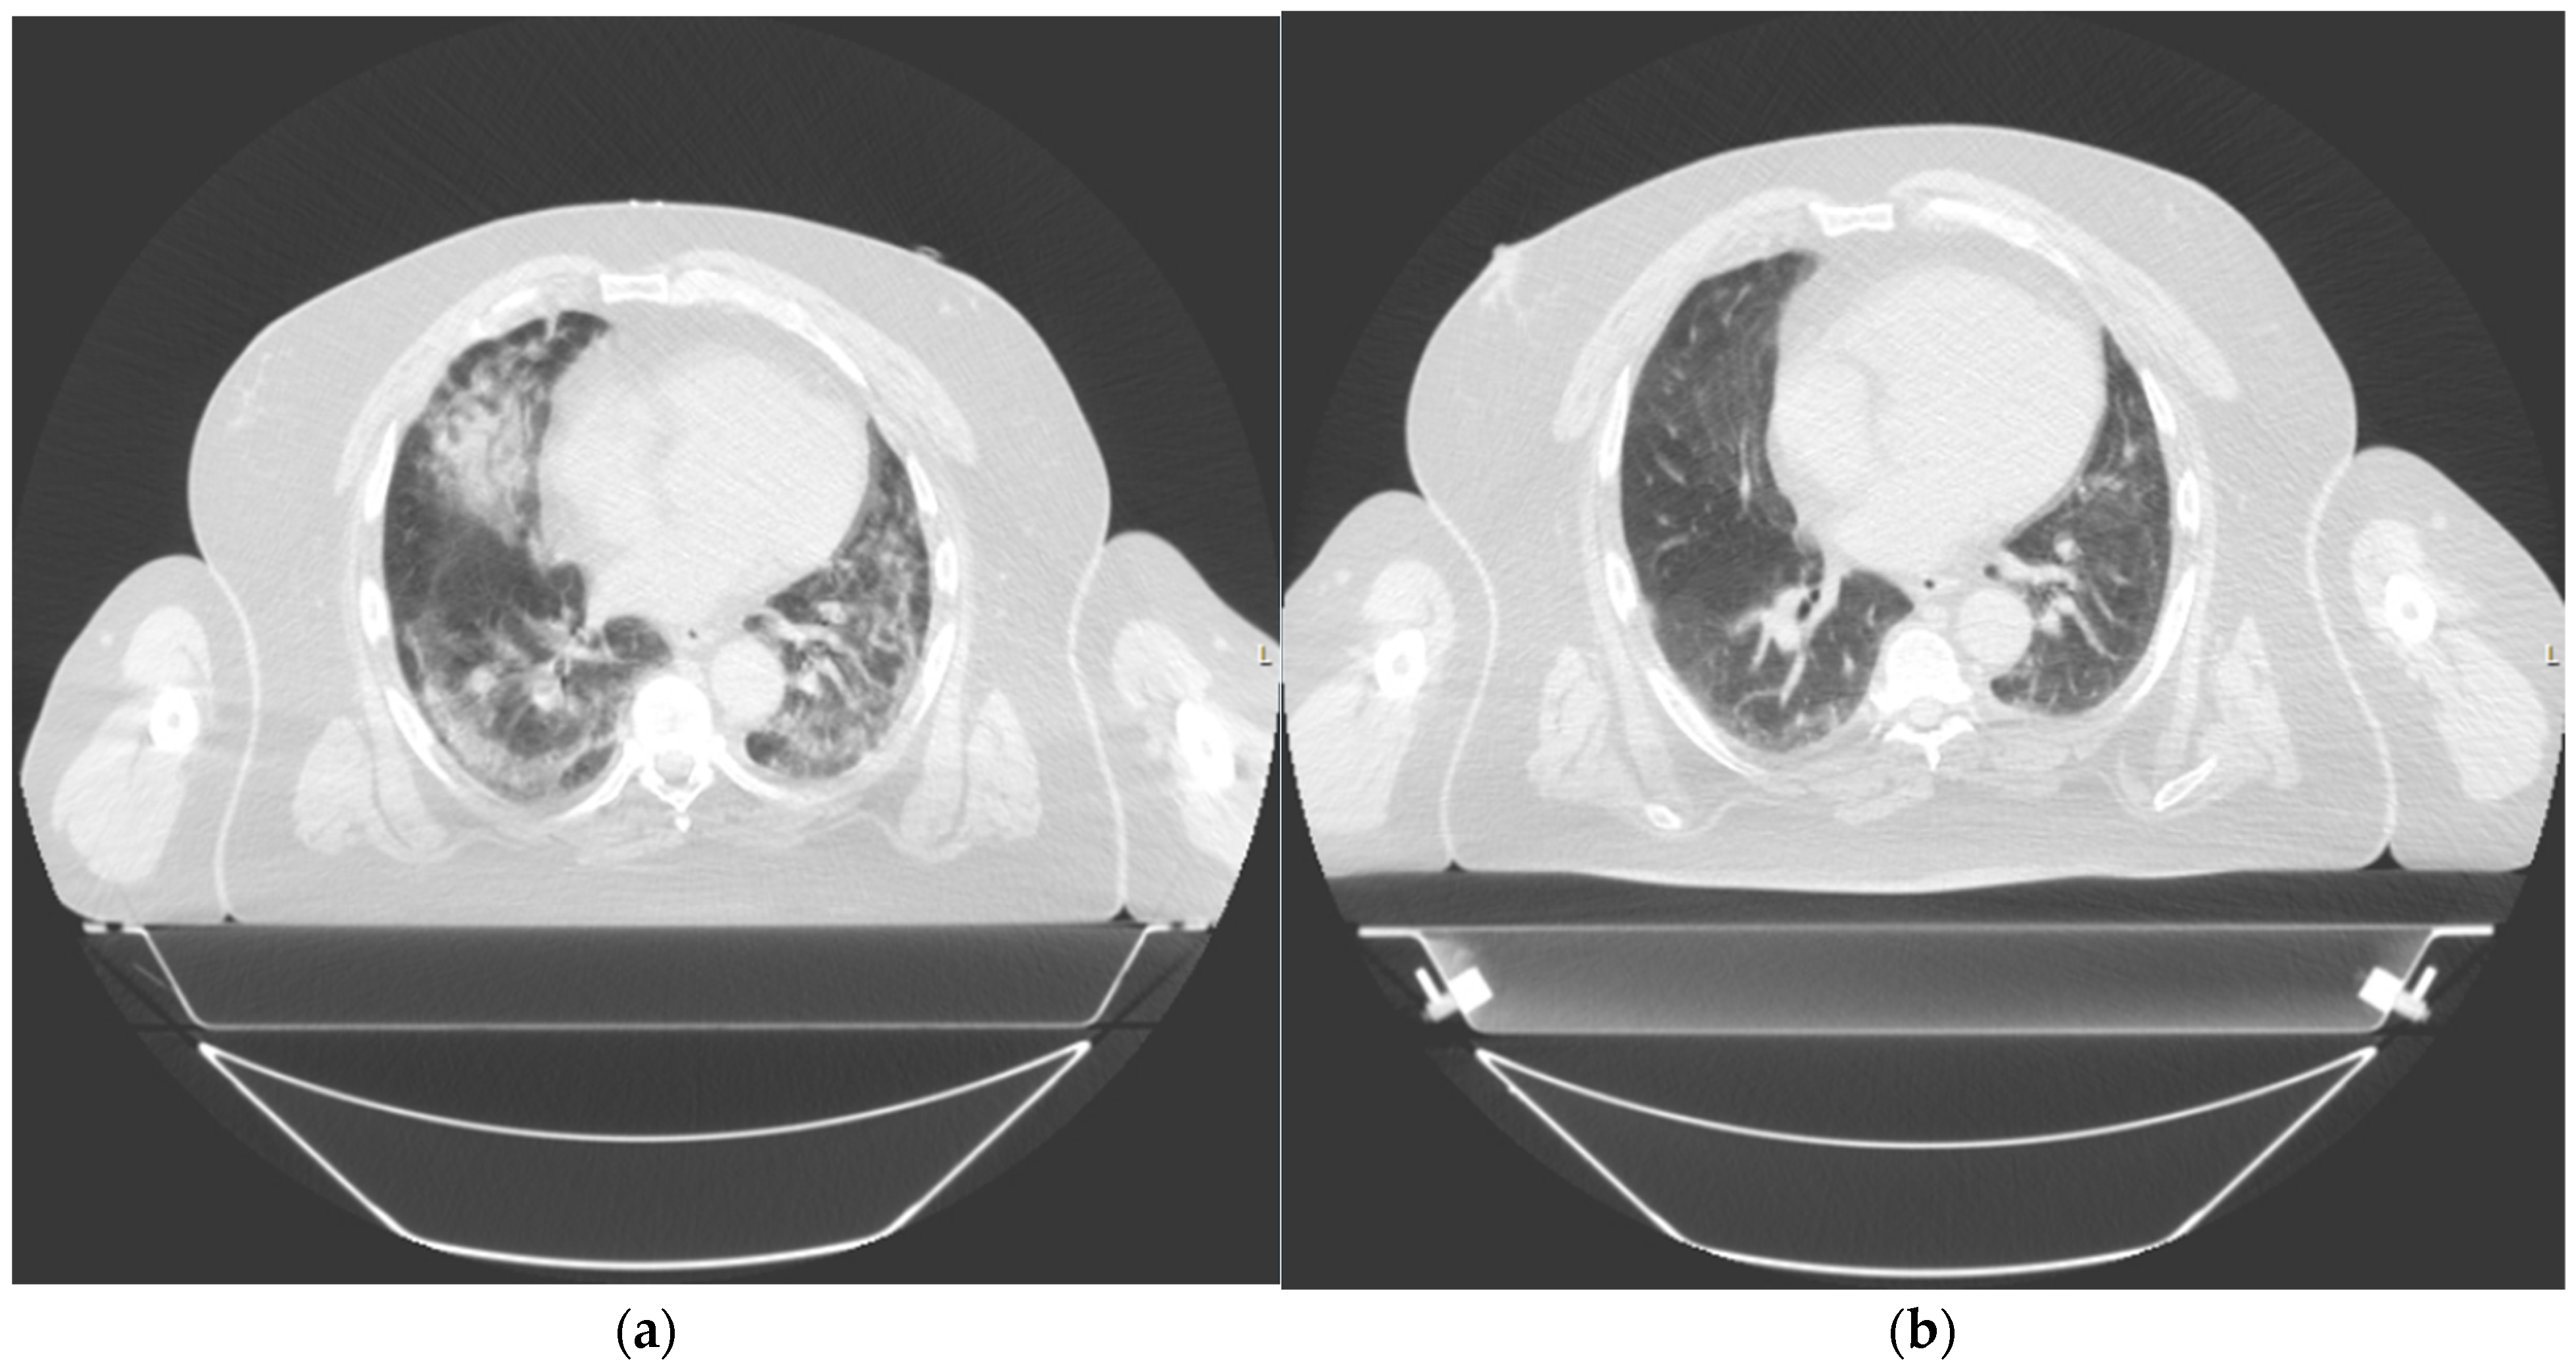

2.1. Patient 1

2.2. Patient 2

3.1. Patient 1

3.2. Patient 2